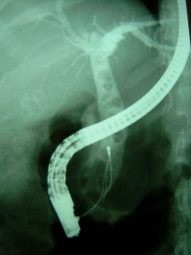

Coledocolitiasis múltiple y extracción

Envíado por Dr. Carlos Miguel Zavaleta Consuegra